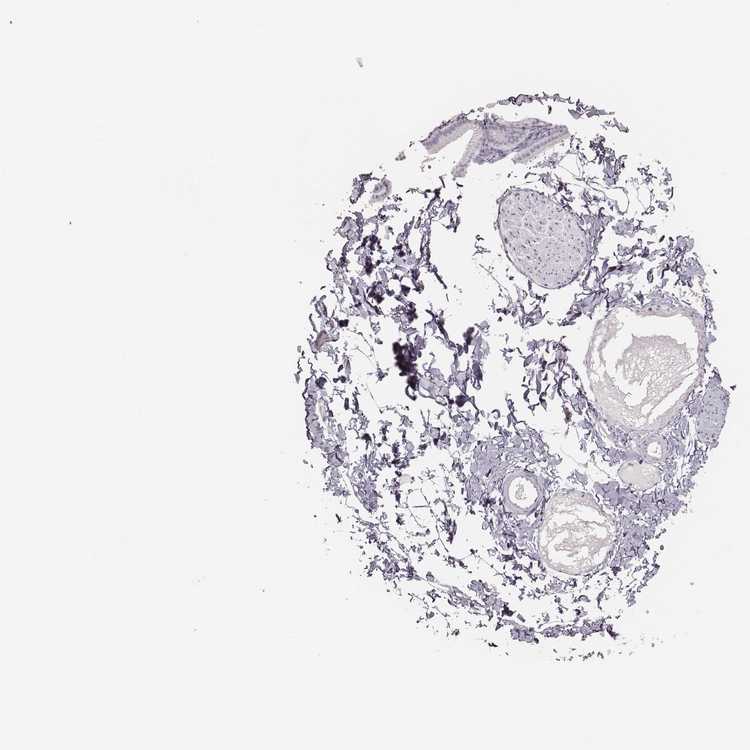

SOFT TISSUE 1 - Antibody stainingi

Antibody staining in the annotated cell types in the current human tissue is reported as not detected, low, medium, or high, based on conventional immunohistochemistry profiling in selected tissues. This score is based on the combination of the staining intensity and fraction of stained cells.

Each image is clickable and will lead to virtual microscopy that enables deeper exploration of all samples and also displays staining intensity scores, fraction scores and subcellular localization as well as patient and tissue information for each sample.

Antibody HPA055194Antibody HPA072208

Chondrocytes -Not detected

Fibroblasts Not detected-

SOFT TISSUE 2 - Antibody stainingi

Fibroblasts Not detectedNot detected

Peripheral nerve -Not detected